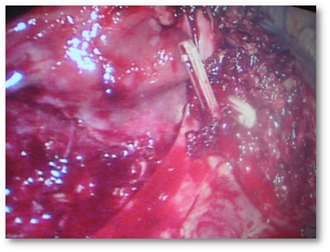

腹腔镜肝叶切除手术图组:

![]() |

肝肿瘤CT片 |

分离肝脏 |